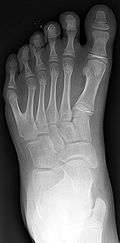

Left foot with postaxial polydactyly of 5th ray

Classification is performed by using x-ray imaging to see the bone structures.[15]